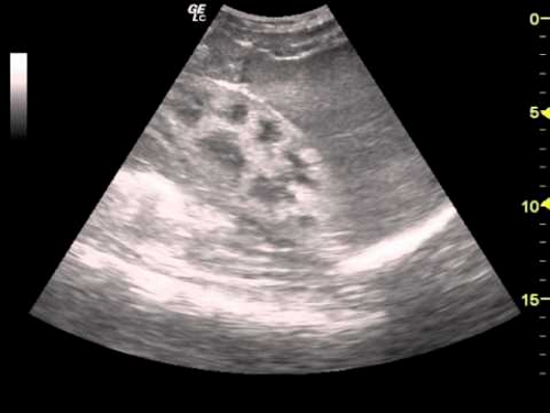

Уратный нефролитиаз обычно имеет двусторонний характер. Камни не видны на рентгеновских снимках, поэтому для диагностики используется ультразвуковое исследование. В период ремиссии изменения в составе мочи отсутствуют. При почечной колике могут появляться кровянистые включения и выход конкрементов с мочой. Длительное обострение может привести к пиелонефриту и постренальной почечной недостаточности.

| Изменения на УЗИ почек (увеличение, снижение эхогенности) | Все стадии | Лечение основного заболевания |

Нефропатия может проявляться различными симптомами, такими как отеки, повышенное артериальное давление, изменения в мочеиспускании (например, частота, цвет или запах мочи), а также общая усталость и слабость. Для точной диагностики важно обратиться к врачу, который проведет анализы крови и мочи, а также может назначить ультразвуковое исследование почек.